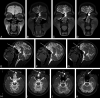

CE-MRC has been in use for the past 15 years and was reported to be a useful method in the evaluation of CSF disorders and hydrocephalus. The use of CE-MRC in conjunction with other MR imaging techniques has been shown to be effective in selected cases for the evaluation of several disorders of cerebrospinal system. CE-MRC has certain advantages over other cisternographic studies with fewer side effects if performed properly. Although intrathecal Gd administration is not widely accepted yet, several recent studies have reported the safety of small-dose intrathecal gadolinium injection. In this review, we describe CE-MRC and review recent applications in several clinical conditions.